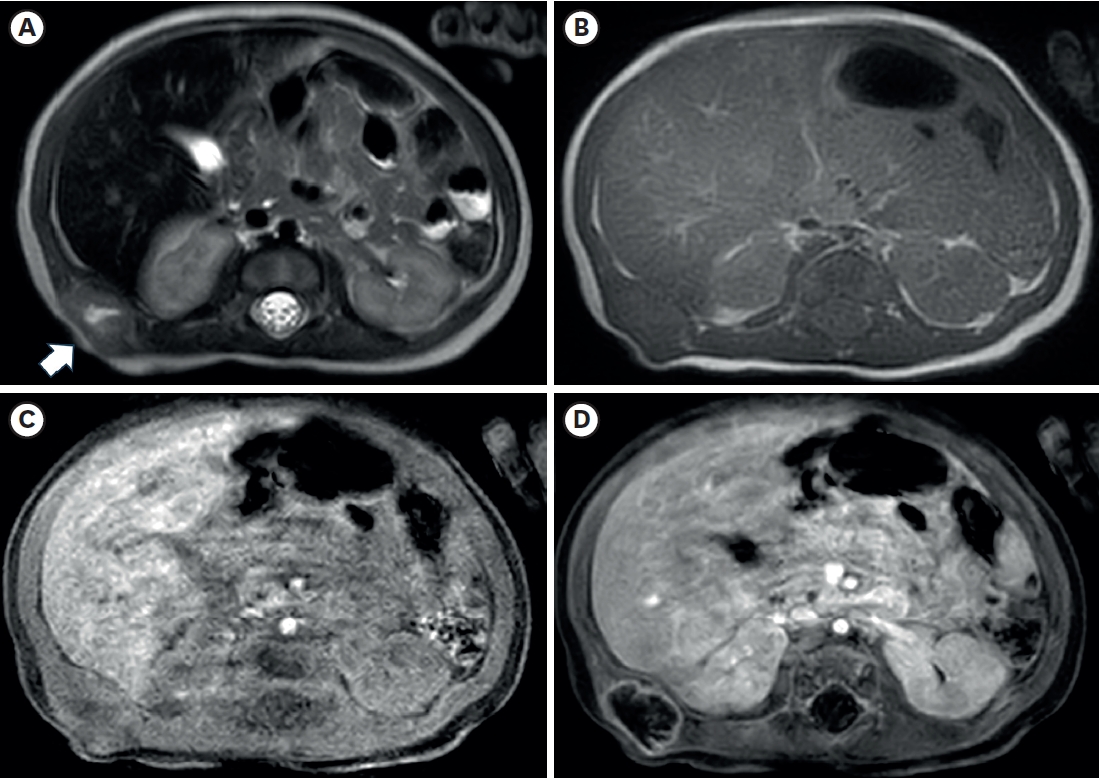

Fig. 3.

Histopathological findings. (A) Light microscopy reveals poorly circumscribed mass-forming lesions surrounded by skeletal muscle. No hemorrhage or necrosis was identified. However, central degeneration was noted (HE, 4×). (B) The lesion has an ill-defined border, and some entrapped skeletal muscle fibers are noted (arrow). The lesion is mainly composed of spindled cells. The stroma of the lesions is collagenous and myxoid (HE, 100×). (C) Most of the spindled cells show no atypia or mitosis. Minimal inflammatory cells are noted (HE, 200×). (D) High-power view of the lesion reveals a few ganglion-like cells, a histological characteristic of proliferative myositis (arrow) (HE, 400×). (E) Spindled cells were positive for smooth muscle actin, supporting fibroblastic proliferation, the other histologic finding of the tumor. (F) Desmin staining confirmed entrapped atrophic skeletal muscle fibers, suggesting tumor extension between individual muscle fibers (immunohistochemistry, 200×).

HE, hematoxylin and eosin.

Histopathological findings (

Fig. 3) showed a few ganglion-like cells and fibroblastic proliferation, which were compatible with PM characteristics. There was no hemorrhage or necrosis, but central degeneration was noted.

Typical histopathologic findings of PM include the proliferation of dense spindle-shaped fibroblasts and ganglion-like giant cells, which resemble rhabdomyoblasts. Their presence can lead to a misdiagnosis of sarcoma [

13]. This case also had these two characteristics, supporting the diagnosis of PM.